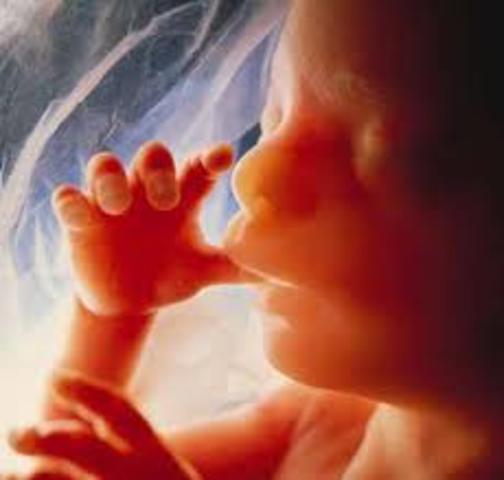

• 12 SEMANA

12 SEMANA

El feto mide 9cm. y pesa entre 15 y 20 gramos. Comienzan a esbozarse las uñas. Aparece en el feto el reflejo de succión. Abre y cierra la boca. Frunce la frente, patea, extiende los dedos de los pies, cierra las manos y puede girar la cabeza. La placenta, que permite la nutrición del feto por medio de nutrientes que le llegan desde la sangre materna, adquiere forma redonda y en su parte central se inserta el cordón umbilical.